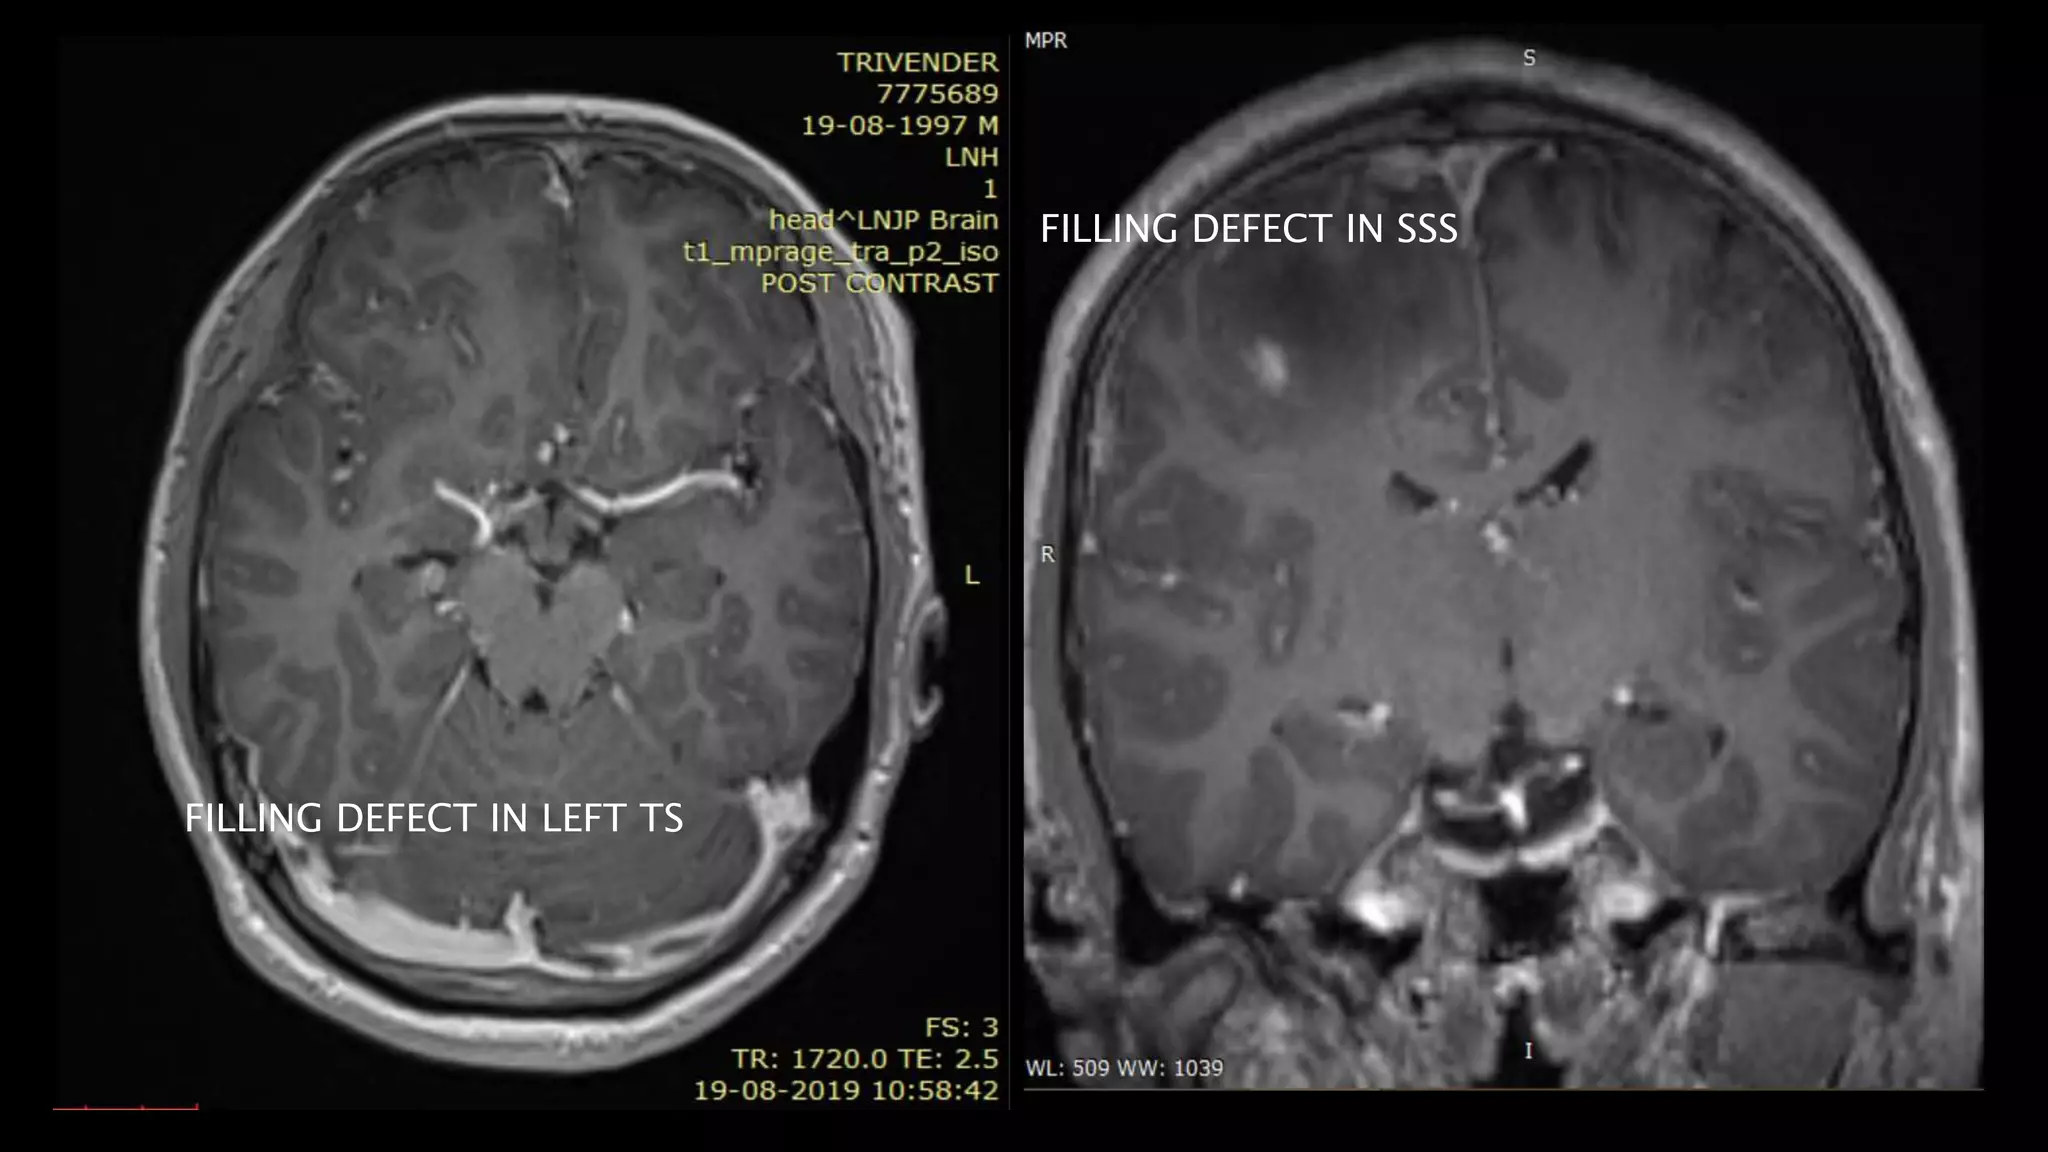

Thrombus in SSS

FILLIN

G

DEFEC

T IN

SSS

FILLING DEFECT IN SSS

FILLING DEFECT IN LEFT TS

• #141 These IS THE axial T2shows absence of normal flow void and hyperintense thrombus in SSS and TOF3d multislab image shows filling defect in SSS

• #142 On post contrast axial image, there is filling defect in the left transverse sinus as well …and in SSS as visible in this coronal secttion

• #144 In cases of DST ,IT IS THE dst THAT extends